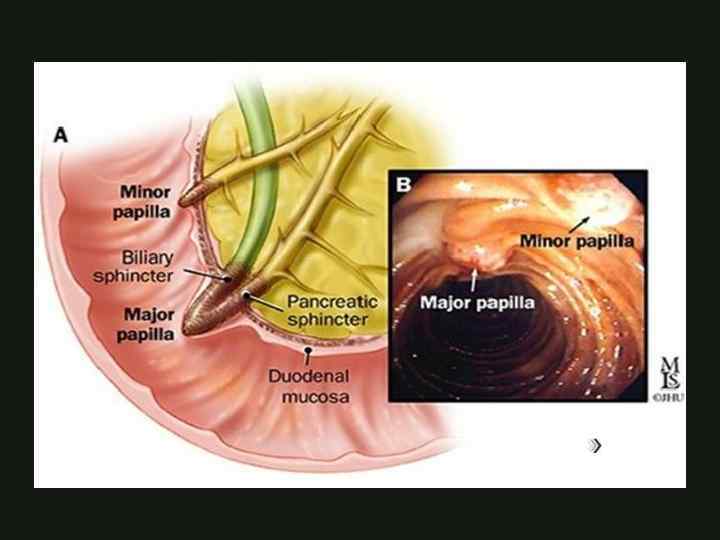

ЭМБРИОЛОГИЯ формируется на 4 неделе гестации из печёночного отростка вентральный зачаток формирует часть головки поджелудочной железы, крючковидный отросток и Вирсунгов проток КАФЕДРА ХИРУРГИИ МОСКОВСКОГО ФАКУЛЬТЕТА

ЭМБРИОЛОГИЯ формируется на 4 неделе гестации из печёночного отростка вентральный зачаток формирует часть головки поджелудочной железы, крючковидный отросток и Вирсунгов проток КАФЕДРА ХИРУРГИИ МОСКОВСКОГО ФАКУЛЬТЕТА

ЭМБРИОЛОГИЯ дорсальный зачаток формирует тело, хвост, часть головки поджелудочной железы и Санториниев проток на 37 день гестации формируется единый орган КАФЕДРА ХИРУРГИИ МОСКОВСКОГО ФАКУЛЬТЕТА

ЭМБРИОЛОГИЯ дорсальный зачаток формирует тело, хвост, часть головки поджелудочной железы и Санториниев проток на 37 день гестации формируется единый орган КАФЕДРА ХИРУРГИИ МОСКОВСКОГО ФАКУЛЬТЕТА